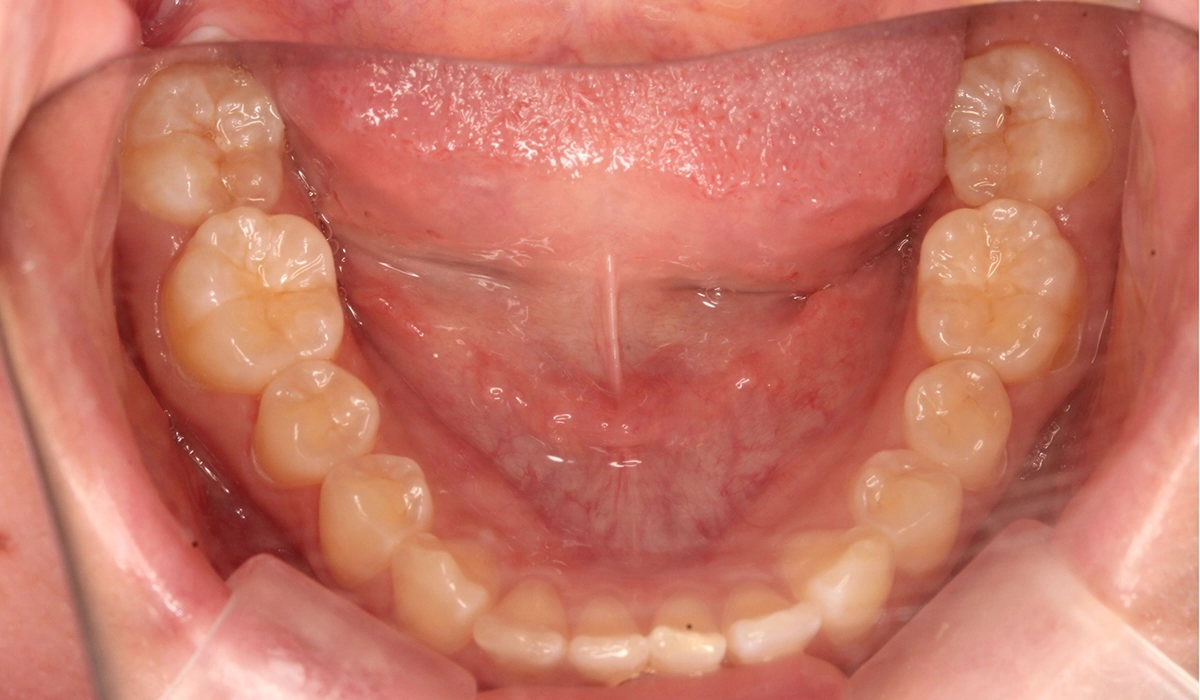

術前:下顎

術後:下顎